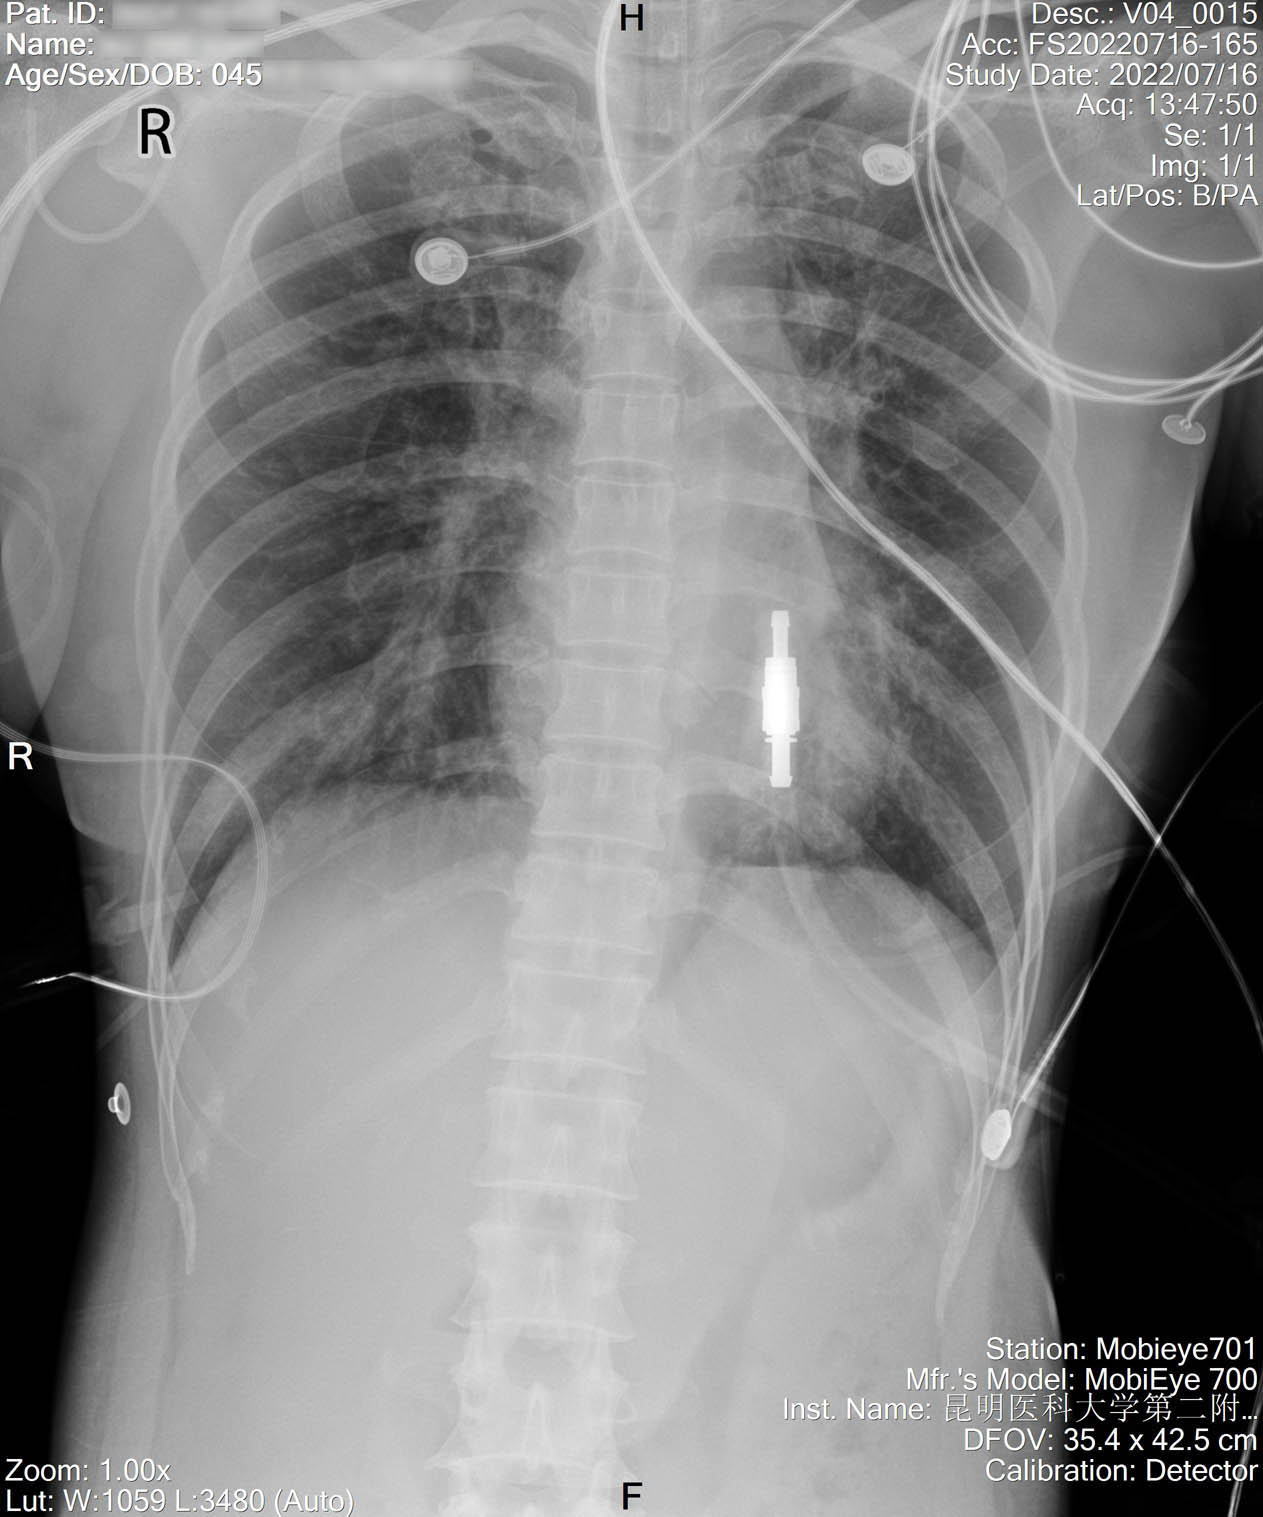

2022-07-29_胸片